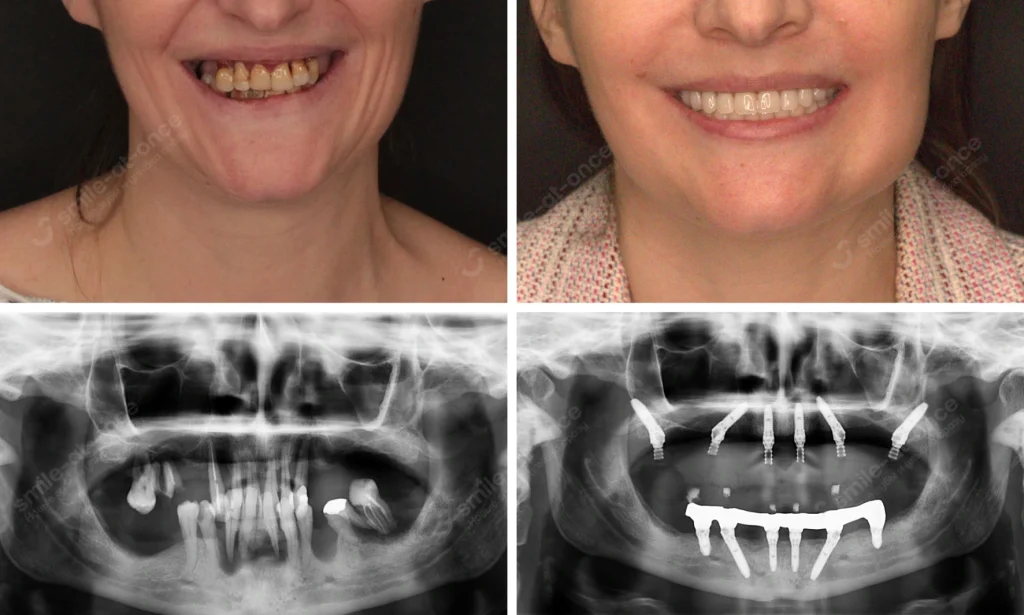

До и после имплантации зубов